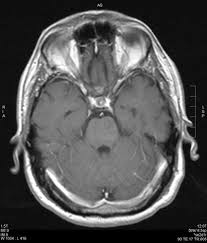

Clippers Syndrom - Autoimmune Brain Disease / Clippers syndrome (chronic lymphocytic inflammation with pontine perivascular enhancement responsive to steroids) is a recently described rare disease affecting the central nervous system.

Review of an increasingly recognized entity within. Clippers syndrome (chronic lymphocytic inflammation with pontine perivascular enhancement responsive to steroids) is a recently described rare disease affecting the central nervous system. Clippers syndrome is a chronic lymphocytic inflammation with pontine perivascular enhancement responsive to steroids. Erste fälle wurden in den usa diagnostiziert. Chronic lymphocytic inflammation with pontine perivascular enhancement responsive to steroids. Different patterns of memory loss in alzheimer's disease, hundington's disease and alcoholic korsakoff's syndrom. Chronic fatigue syndrom in community. Moss m.b., m.s.albert, n.butters et al.

Clippers Ein Zunehmend Diagnostiziertes Syndrom Springermedizin De

Clippers Ein Zunehmend Diagnostiziertes Syndrom Springermedizin De from media.springernature.com